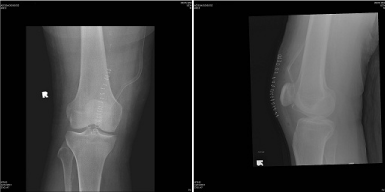

A 53 year-old male presented with history of fall down over his flexed knees while descending from stairs and complaining of bilateral knee pain, swelling and inability to bear weight. He is known to have chronic renal failure secondary to membranous glomerulonephritis for the last 15 years. He is on hemodialysis three times per week since that time. He has history of two rejected renal transplant in the last seven years. Clinical examination revealed bilateral severe effusion around the knee with tenderness to palpation. A palpable left infrapatellar and right suprapatellar gaps are detected. His knees were in 20-30 degrees of flexion with restricted active flexion due to pain and effusion. He has bilateral loss of extensor mechanism. Bilateral knee x-rays showed left knee patella alta with Insall-Salvati ratio of 0.48. Right knee x-ray showed no obvious abnormality with Insall-Salvati ratio of 1.07 (Figure 1–3).

Figure 2 Lateral right knee radiograph showing normal Insall-Salvati.

Figure 3 Lateral left knee radiograph showing patella alta.